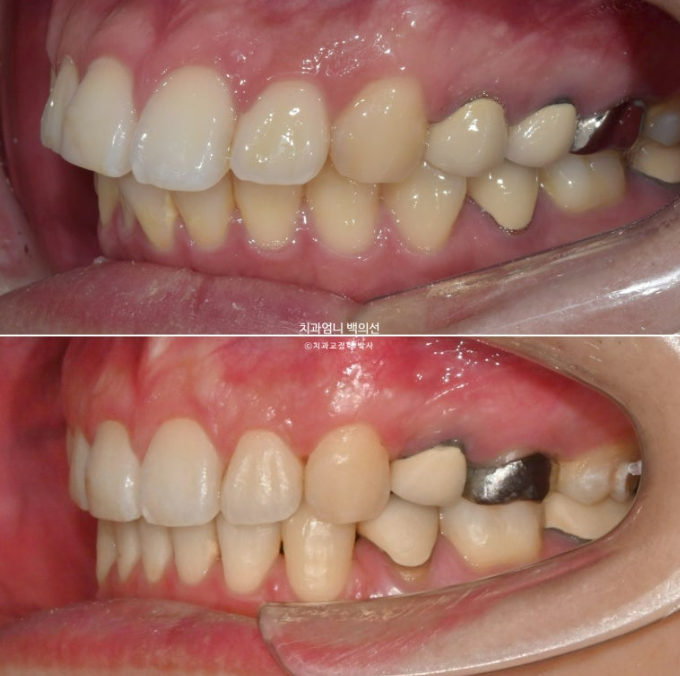

2022.12월 돌출입을 주소로 내원한 환자분 입니다.

앞니 중심선이 어긋나있고 앞니 기울어짐이 보입니다.

2022.12

앞니가 상당히 뻗쳐있는 상태 뻗침과 돌출이 심해서 입이 잘 안다물어지는 상태였고 골격분선상 골격성 2급 부정교합 (무턱)도 있습니다.

앞니가 뻗쳐있는 심한 돌출입은 당연히 발치교정을 해야합니다.

인비절라인 치료 선택하셨고 치료에 들어갔습니다.